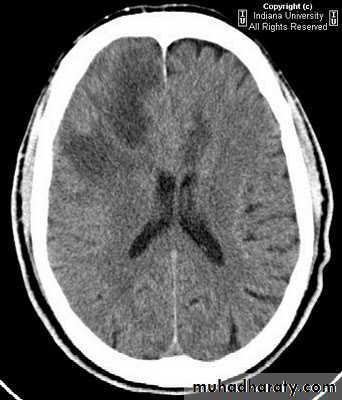

• Associated hydrocephalus.

• Bony changes.

1. If the patient shows signs of compression, or raised intracranial pressure, treat with measures that lower ICP.

2. If an intracranial tumour is associated with hydrocephalus, the hydrocephalus is dealt with first by a ventriculoperitoneal shunt before surgery.